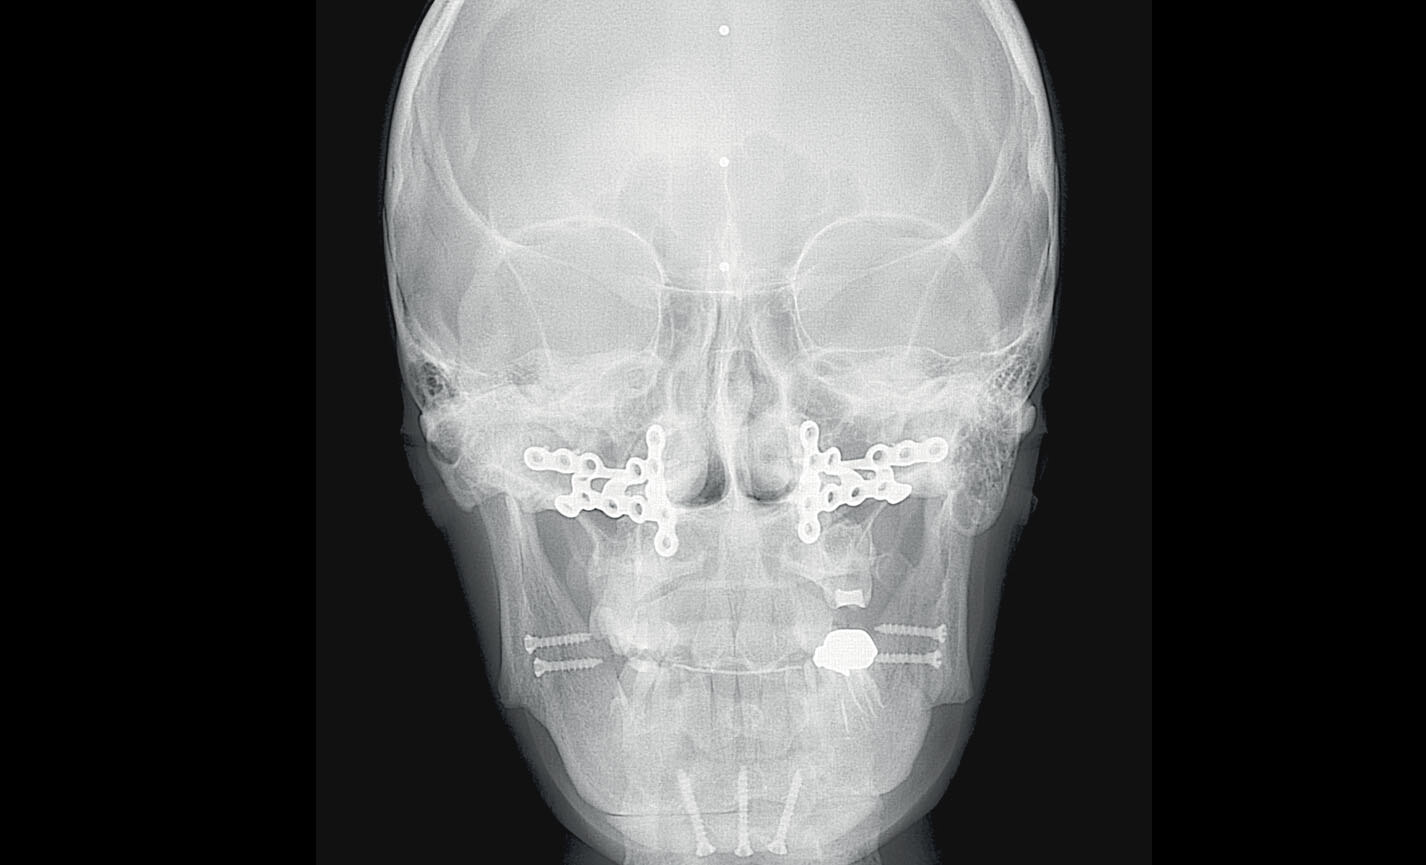

Téléradiographie

Antéro-postérieure : pour investiguer les asymétries et les malocclusions en vue d’un traitement correct.

Applications orthodontiques

Des FOV de 10 cm de diamètre sont nécessaires pour l’étude des troisièmes molaires incluses car, chez un adulte de taille moyenne, la distance entre les troisièmes molaires de droite et de gauche, en incluant leurs racines respectives, le processus alvéolaire et l’os avoisinant, est d’au moins 9 cm. Les champs de vision réduits sont utiles en cas d’analyse de dents incluses ou surnuméraires, pour limiter la dose à la seule région d’intérêt. En effet, pour une planification correcte du traitement, il est fondamental de déterminer la position réelle (vestibulaire ou palatine), possible uniquement avec une analyse 3D, même à très faible dose avec un protocole QuickScan. Le champ de vision complet 13 x 16 cm permet une évaluation minutieuse des voies aériennes supérieures, souvent utile pour compléter une investigation en vue d’un traitement orthodontique qui tienne compte des problématiques oto-rhino-laryngologiques.

Évaluation des implants zygomatiques

Les volumes avec FOV 13 x 8 cm, ou 13 x 10 cm, représentent l’outil idéal pour la planification des implants zygomatiques. En effet, le diamètre de 13 cm est le seul qui permet d’inclure tout le zygoma dans le balayage, sans coupes.